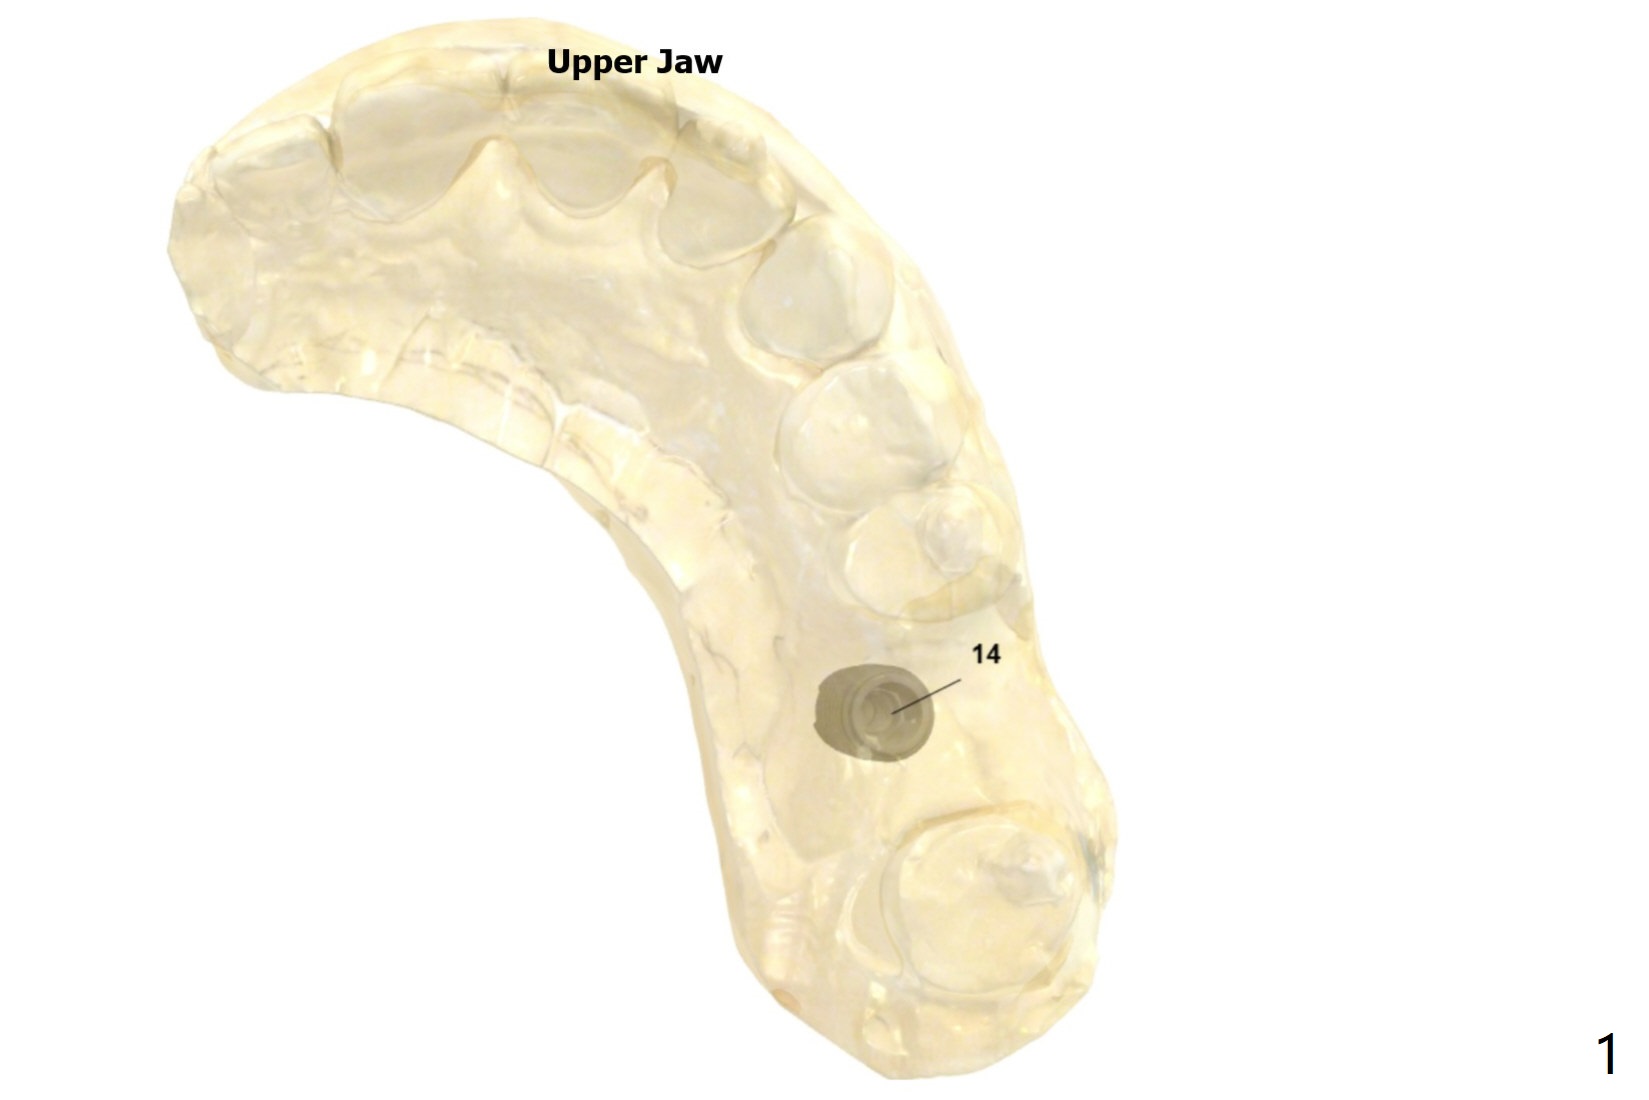

Palatal Placement

Return to Upper Molar Immediate Implant Trajectory II  SP 位点保留后